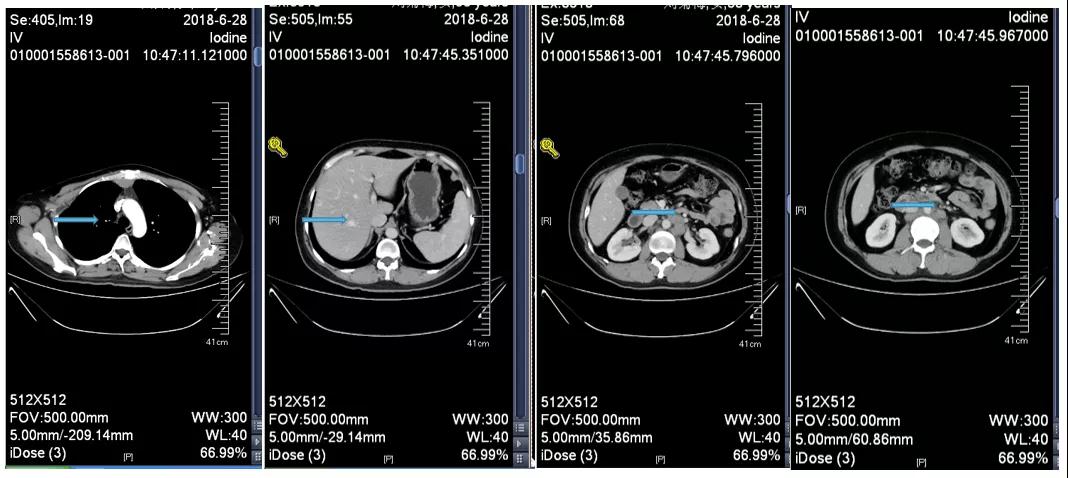

胸腹部增强CT示(2018-6-28):胸骨后占位,肝内异常强化灶,腹膜后肿大淋巴结。

诊断:右乳浸润性癌(rT2N3M1 IV期 HER2过表达型);卵巢转移瘤切除术后;腹膜后淋巴结转移;纵隔淋巴结转移;肝转移。

2018-7-17成功入组ELAINA临床研究(试验方案编号:BO29919),IWRS分配随机号3210。于2018-7-17开始接受T-DM1 3.6mg/kg(252mg)治疗,并间断对其进行疗效评估。现阶段患者PFS达近40个月。

靶病灶:腹主动脉左侧和下腔静脉右侧淋巴结

非靶病灶:肝左叶、肝右前叶下段;纵膈胸骨后淋巴结节;前上纵膈淋巴结;腹膜后小淋巴结

影像学评估-纵膈淋巴结:

影像学评估-肝脏:

影像学评估-腹膜后淋巴结: